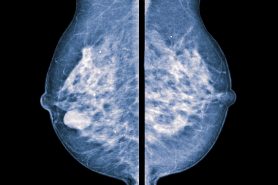

They appear as white spots or flecks on a mammogram but can't be felt during a breast exam. A new group has formed. For women treated for breast cancer in the past, calcifications may also be due.

Eliminate foods that contain methylxanthines, such as coffee,. Unfortunately, there is no absolute way to prevent breast calcifications. Prior radiation therapy for breast cancer.